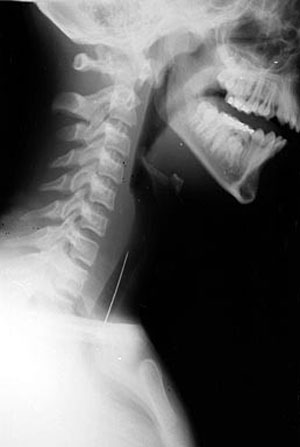

2. Đây là hậu quả của việc cho trẻ tuổi dưới 3 vừa cầm bút vừa chạy. Chiếc bút đã xuyên qua môi trên và lên tới sát mắt. Thật may mắn là ca phẫu thuật lấy dị vật này ra rất thành công và cậu bé hiện hoàn toàn bình thường: